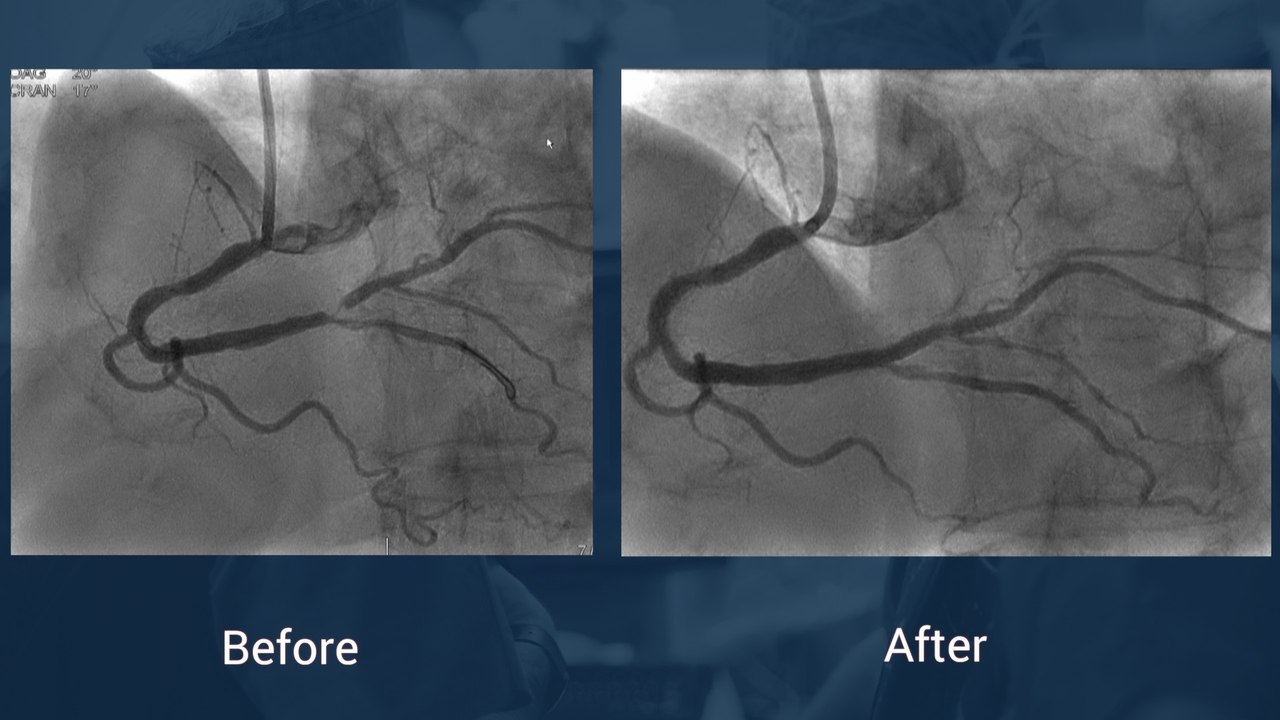

• How to treat Medina 1.0 Left main bifurcation lesion

• In wich case we should use 1 or 2 stent(s) for bifurcation ?

• Rossano F. Very nice result ! Thanks for the operators